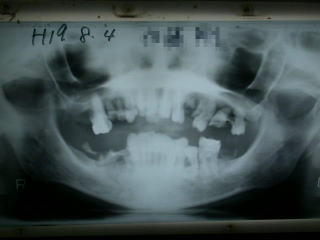

目視で良く確認、レントゲンで位置をさらに良く確認します。

インプラントの位置が、良い位置に植立されたのを確認し、4糸縫合しました。